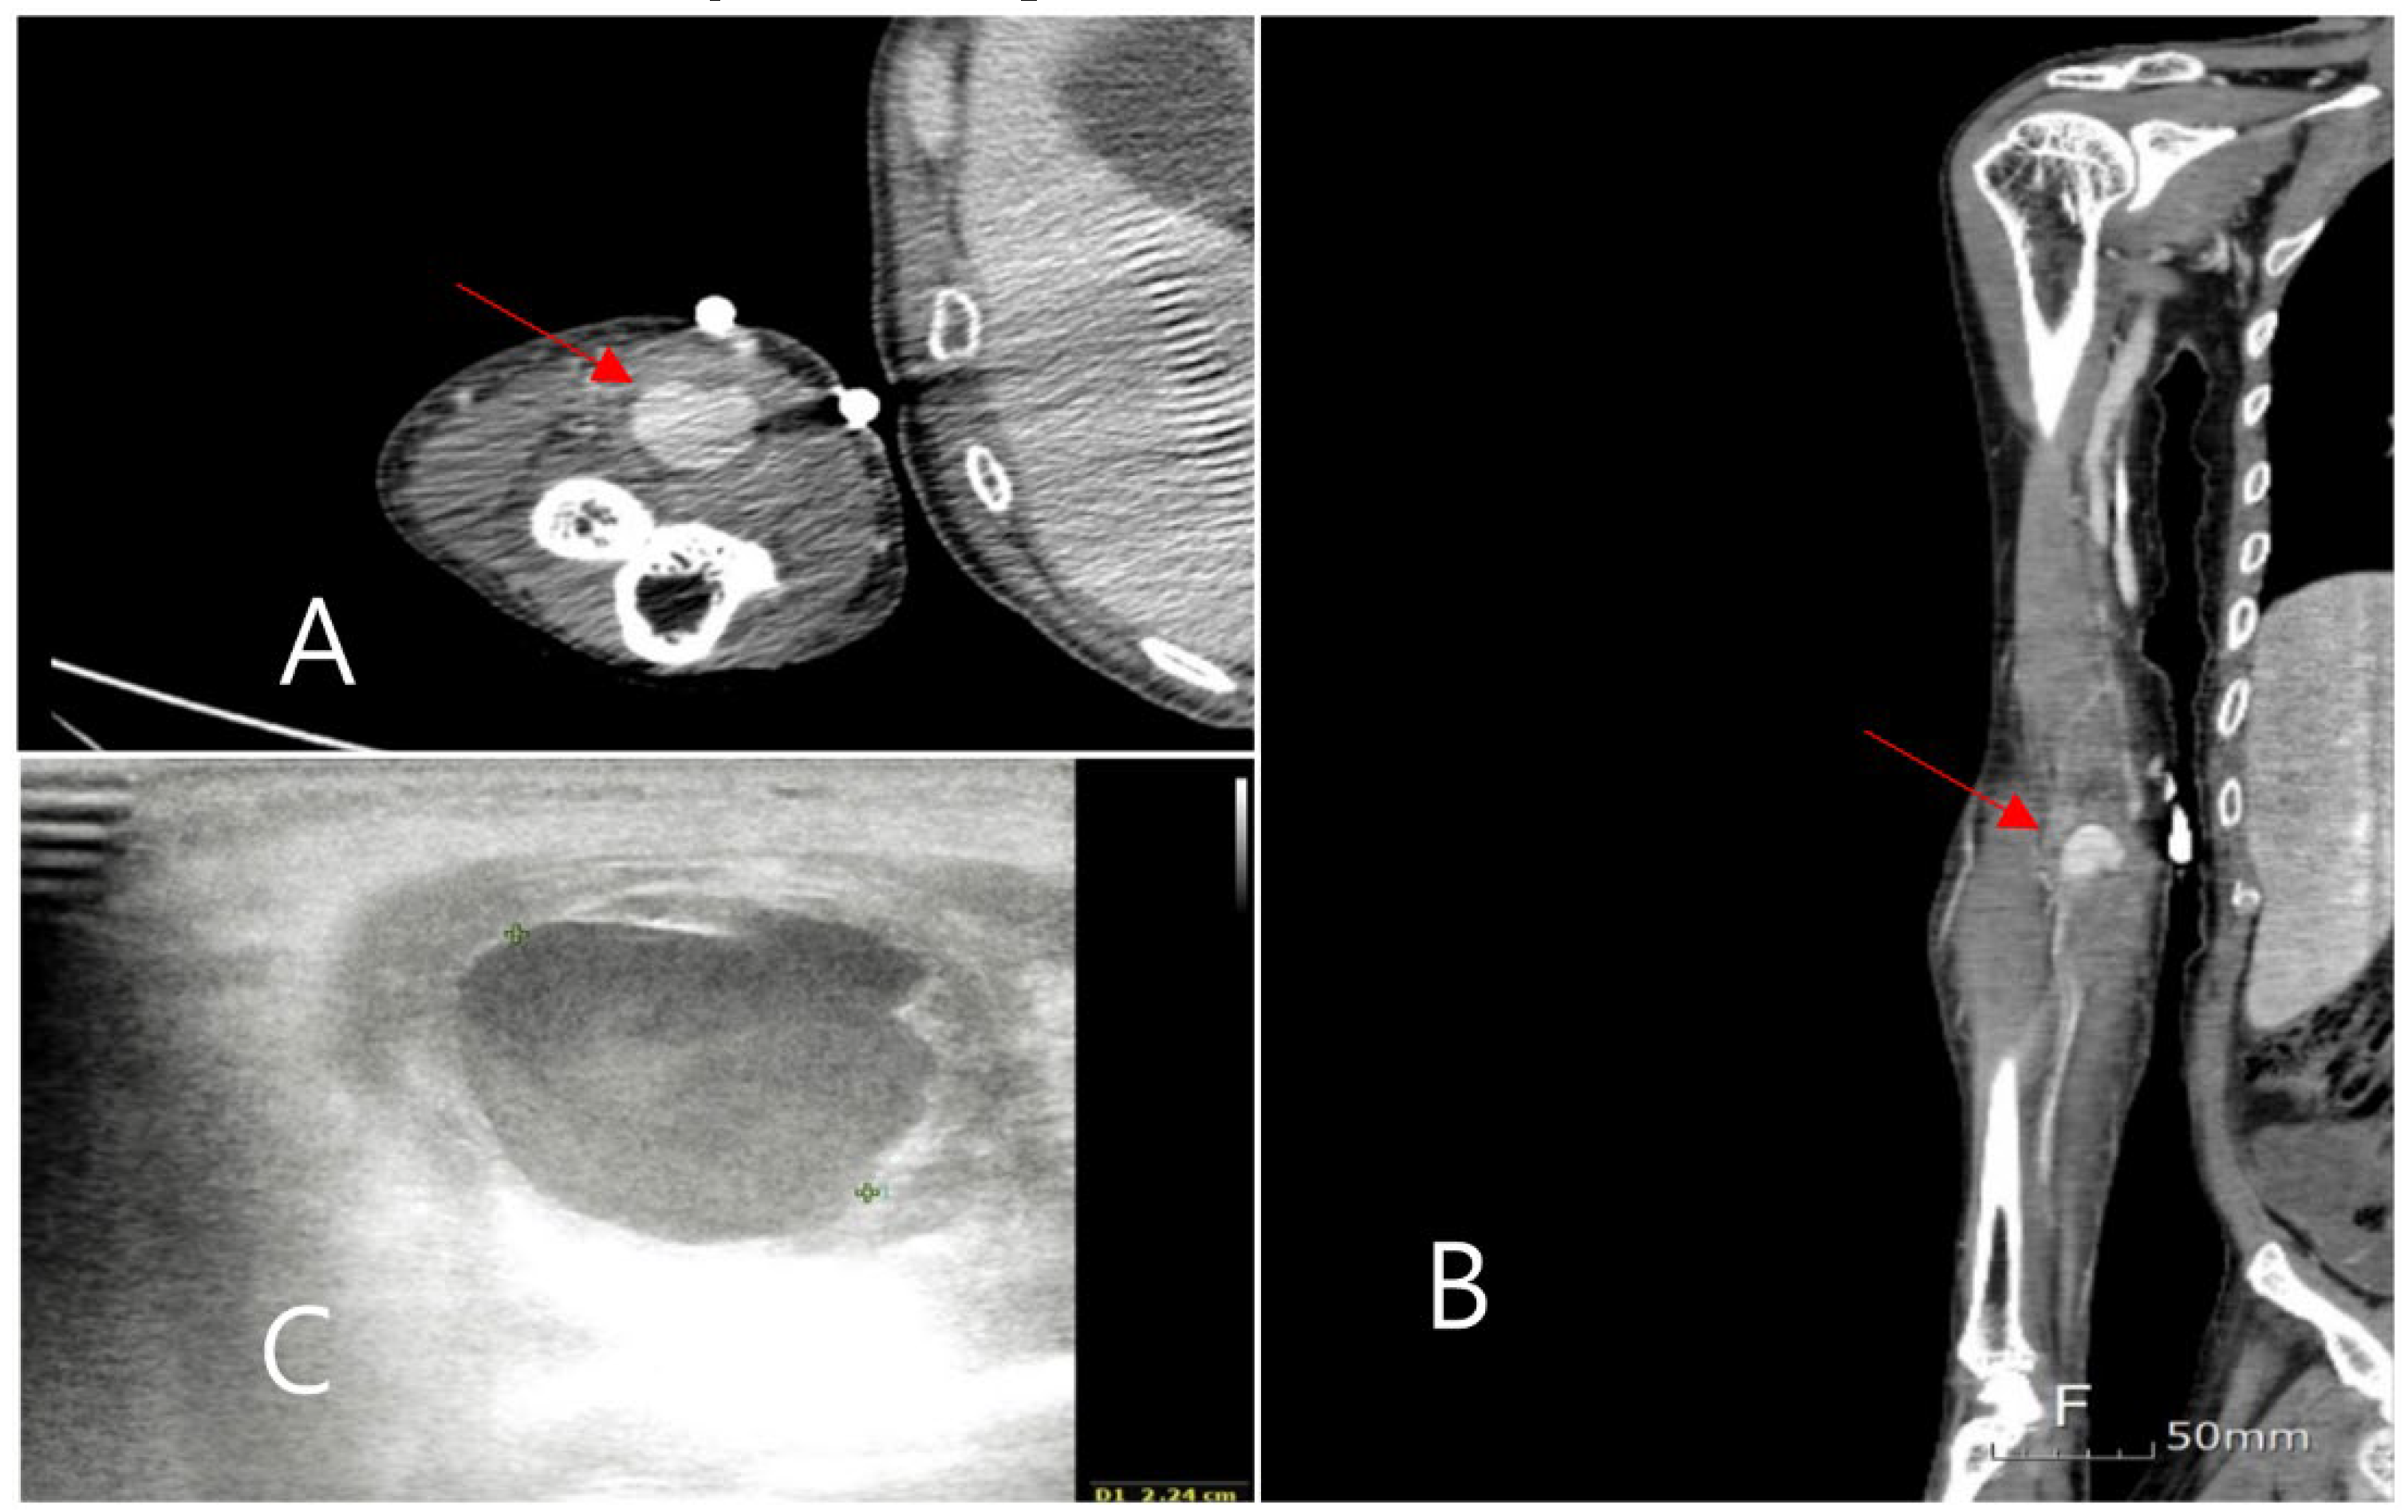

Although the symptoms in the arm disappeared, the spiking fever persisted. To evaluate the other origins of fever, a positron emission tomography (PET) scan of the entire body was performed (Figure 2). It showed high uptake in multiple aneurysms in the abdomen and both lower extremities with normal aorta. A lower extremity CT scan was performed, wherein several aneurysms occluded by a thrombus were observed. A multidisciplinary meeting was held to determine the treatment strategy. Echocardiography was repeatedly performed by another cardiologist. The vegetation in the heart, which was not seen in the previous examination, was observed.

Five months later, the patient was readmitted to the emergency room for a recurrence of a fever of unknown origin. Leukocytosis was observed, but other laboratory examinations revealed no specific findings. To evaluate the focus of the fever, chest and abdominal CT scans were performed, as shown in Figure 3. The findings revealed a contained rupture of the mycotic abdominal aortic aneurysm (AAA). The patient underwent emergency AAA repair using an antibiotic-soaked graft. No complications were observed on the CT scan performed six months after surgery (Figure 4), and the patient has been living without complaints of other symptoms in 1 year follow-up.

Figure 2. multiple peripheral mycotic aneurysms were observed in the PET scan.